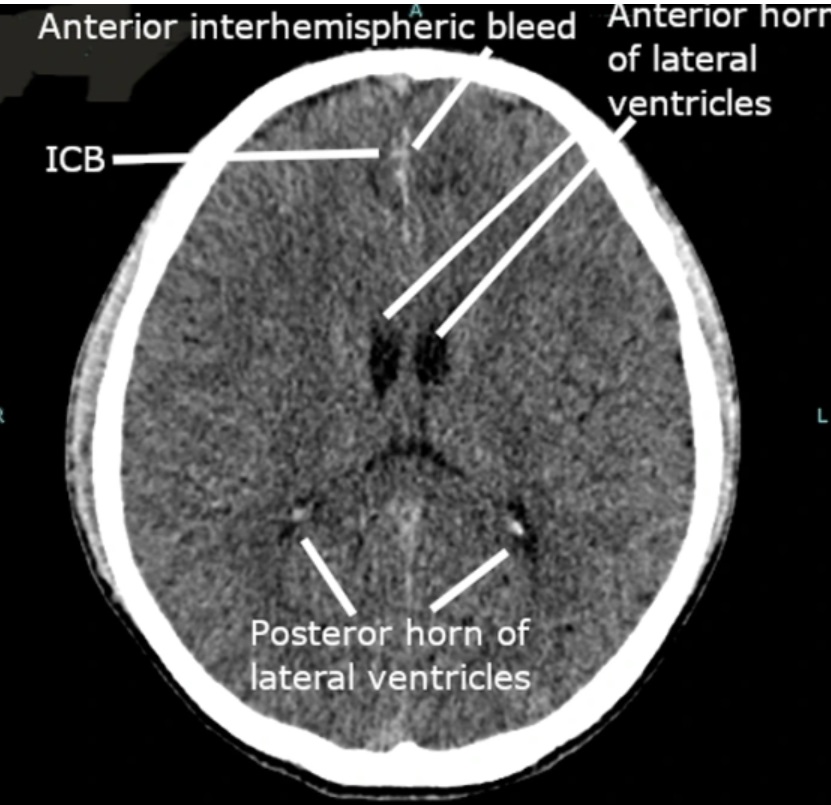

První zobrazovací vyšetření, konkrétně CT mozku, vedlo lékaře k domněnce, že by mohlo jít o vrozené neurogliální cysty, tedy útvary, které bývají často neškodné a nevyžadují agresivní léčbu. Situace se však dramaticky změnila ve chvíli, kdy byl pacient podroben dalším testům, včetně magnetické rezonance.

Podrobnější snímky mozku ukázaly, že útvary neodpovídají typickému obrazu cyst. Znepokojivý nález přiměl lékařský tým k rozšíření diagnostiky o laboratorní testy, které měly odhalit případnou infekci či parazitární onemocnění.